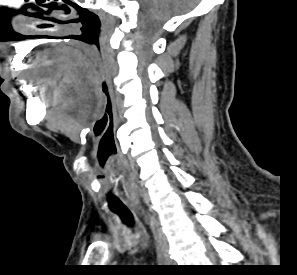

Используемые в нашей клинике томографы, благодаря своему оснащению, позволяют получать снимки высокого качества и детализации за короткий промежуток времени, что минимизирует уровень лучевой нагрузки на организм. Используя полученные данные, аппараты создают трехмерные реконструкции анатомической зоны. Это дает возможность наглядно оценить пространственное соотношение лимфатических узлов и близлежащих органов, выявить прорастание в окружающие ткани, особенно при образовании цепочек, пакетов и конгломератов лимфоузлов.

Для повышения качества визуализации лимфоузлов, особенно при подозрении на онкологических процесс, исследование проводится с внутривенным болюсным контрастированием. Контрастный препарат, содержащий йод, вводится в вену с помощью автоматического шприца. Распространяясь по сосудистой системе, препарат накапливается в патологических очагах, в том числе, в измененных лимфоузлах, и увеличивает их яркость на КТ-изображениях. Методика контрастирования помогает выявлять опухоли минимальных размеров, проводить дифференциальную диагностику между доброкачественными и злокачественными новообразованиями и воспалительными изменениями.

Мультиспиральная КТ позволяет оценить размеры лимфатических узлов, выявить деформацию их контуров, неоднородность структуры, установить точную локализацию, взаимодействие с близлежащими органами и окружающими тканями, обнаружить инфильтрацию прилегающих структур.